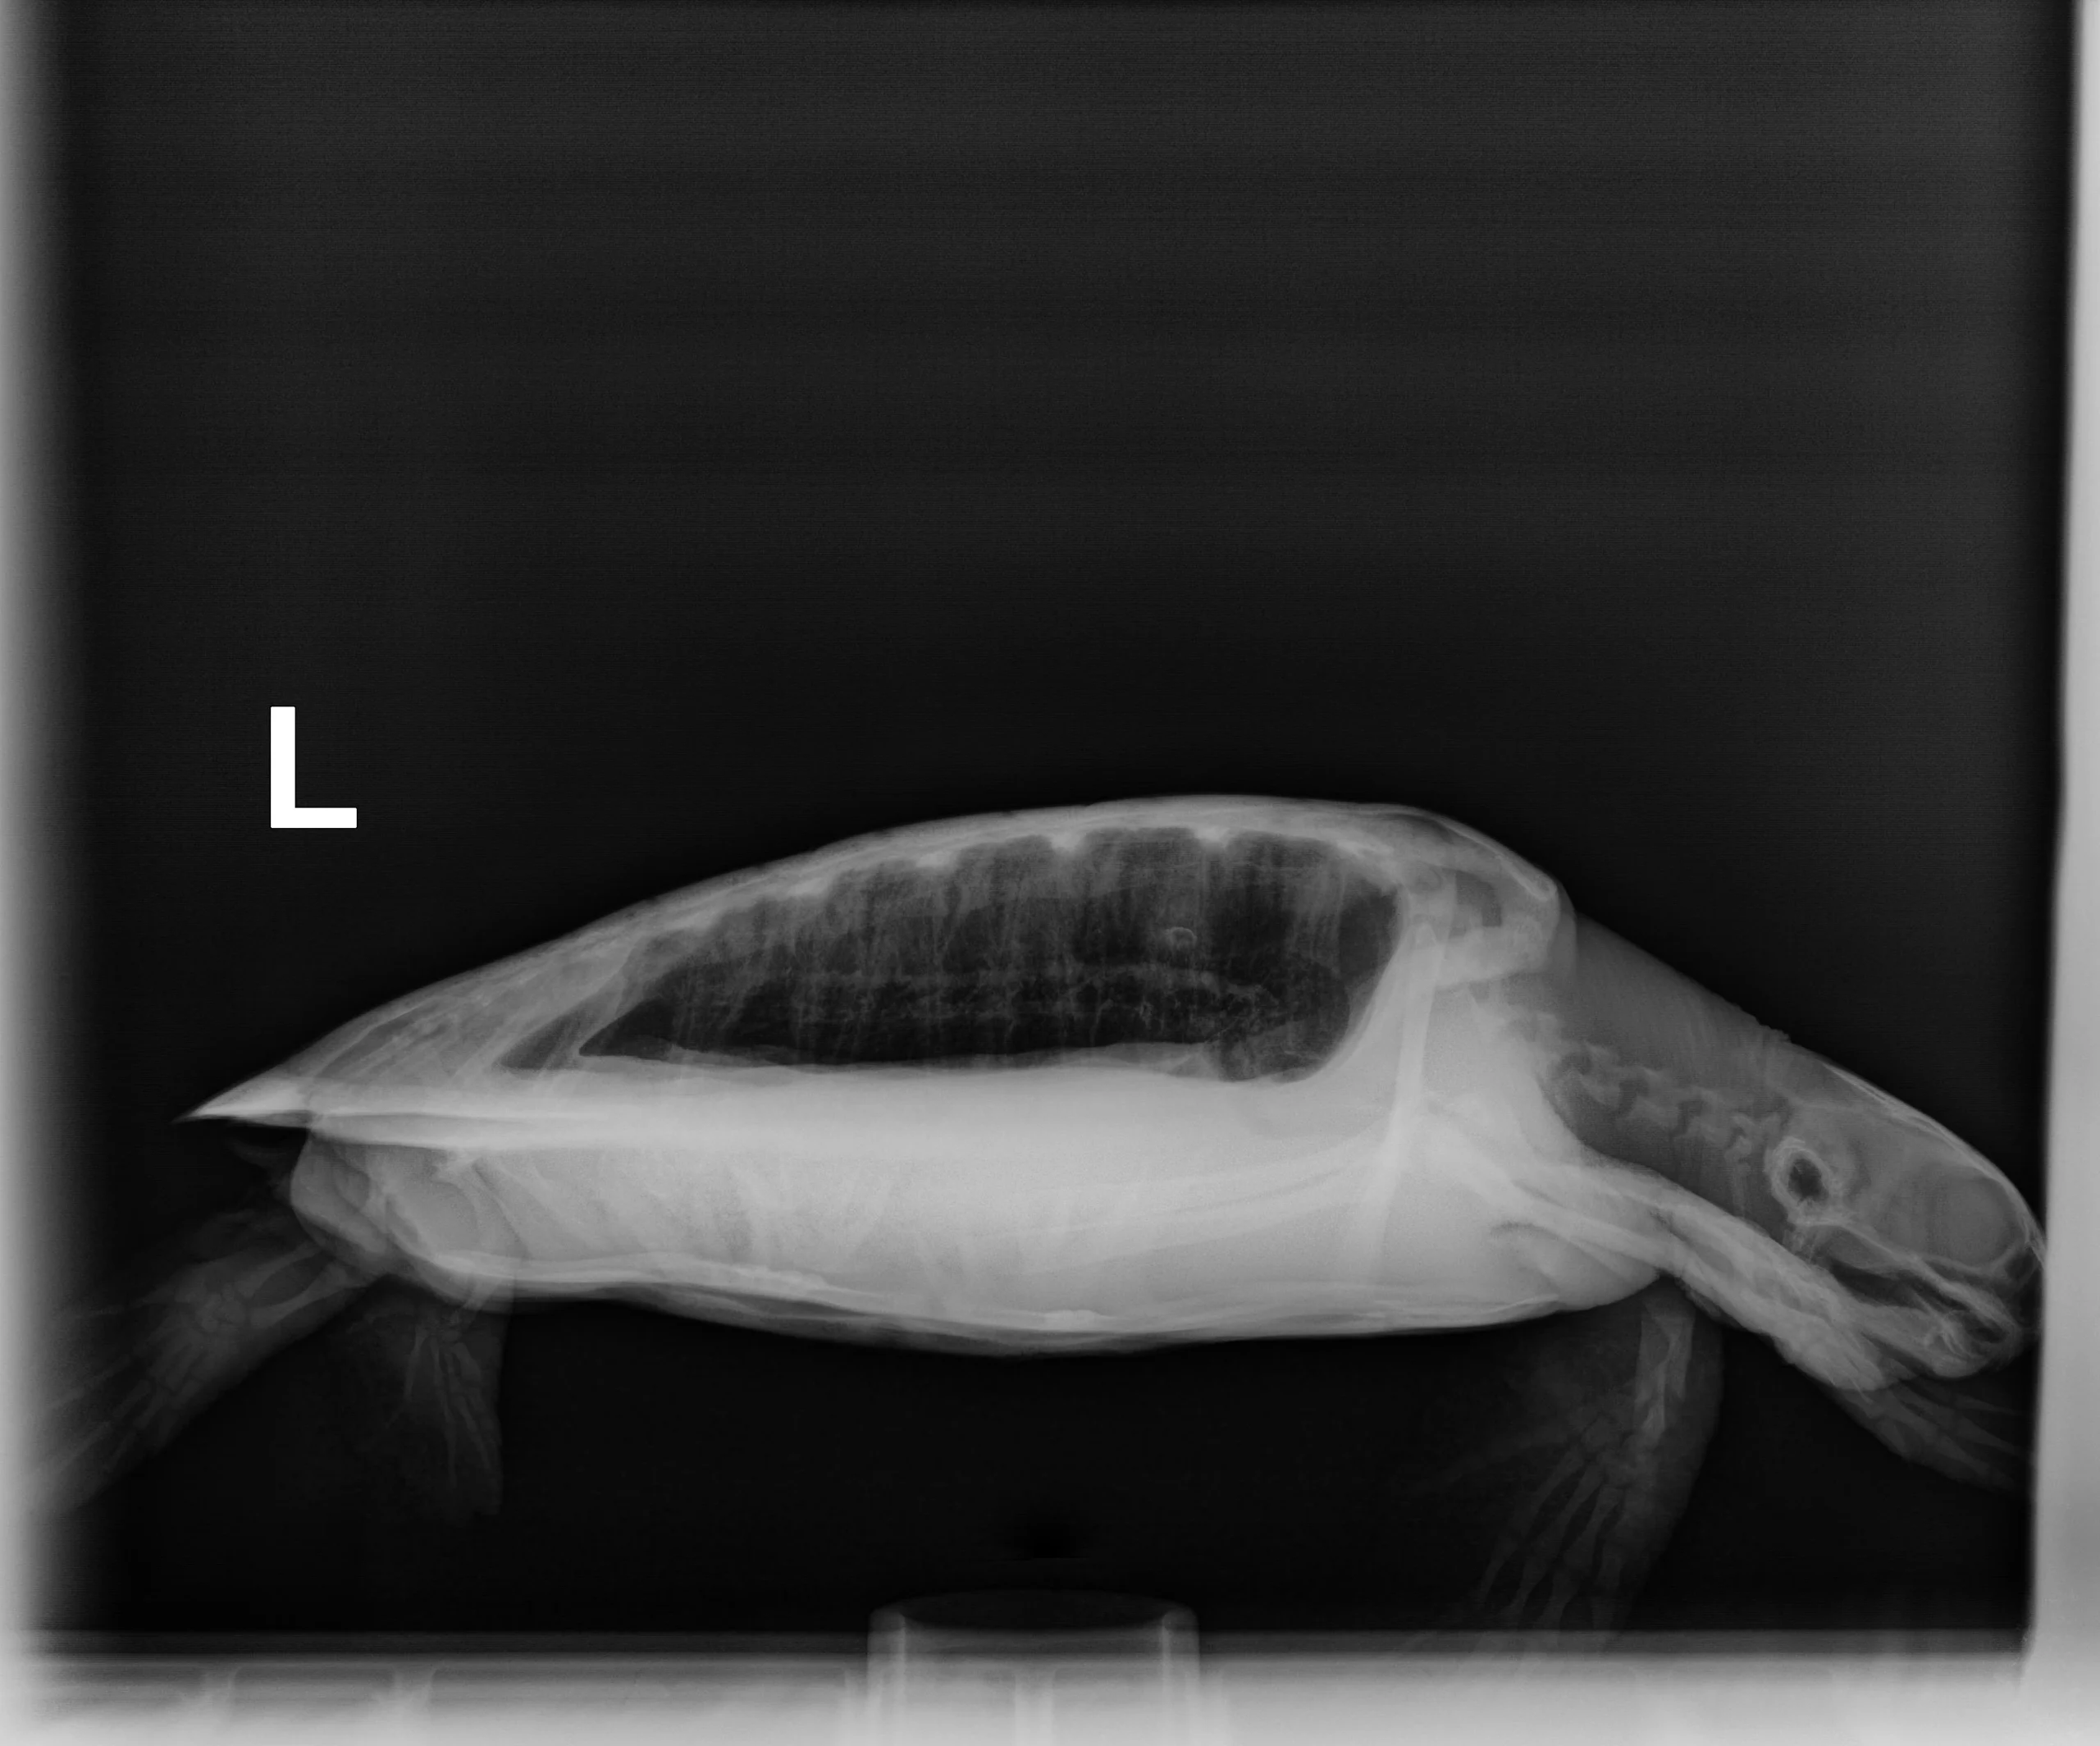

2.1 kg juvenile Atlantic Green

Patient Injuries

Mouth/Beak: Clean – a few small nicks on the beak

External Carapace Notes: Heavy epibiota load

Plastron: Two moderate abrasions and one minor abrasion. one barnacle

Head/Flippers/Soft Tissue: Abrasions to the underside of the left front flipper